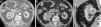

Características particulares de los componentesRadio (R)Este componente representa el diámetro máximo del tumor en cualquier plano. La importancia de la variable en el pronóstico y manejo de los tumores renales es bien conocida, y se utilizó como referencia el sistema de puntuación TNM del año 2002, asignando un punto a las lesiones menores o iguales a 4cm, dos puntos a aquellas entre 4 y 7cm y tres puntos a las mayores o iguales a 7 cm10. Consideramos que la mejor fase para su valoración es la nefrográfica, ya que el realce homogéneo del parénquima mejora la delimitación del tumor (fig. 1).

Componente R: diámetro tumoral máximo (líneas blancas), elegido en cualquiera de los planos. La TCMC del abdomen con contraste endovenoso, en fase nefrográfica, en planos (a) axial, (b) coronal y (c) sagital, presenta una lesión con un diámetro mayor en el plano coronal (40,3mm), por lo que se le asigna un punto. En el plano axial mide 33,4mm y en el sagital 30,5mm.